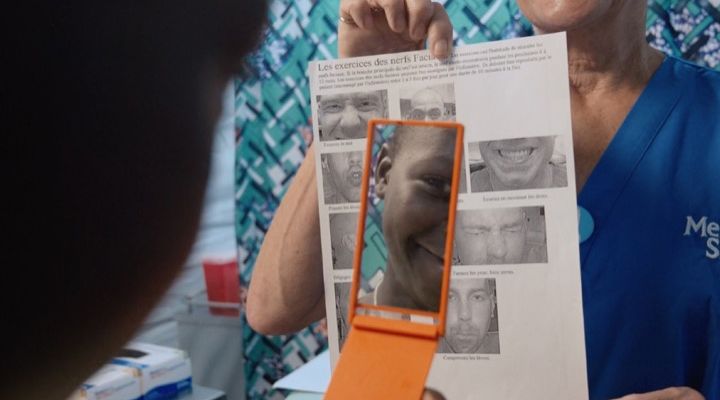

Reunited

When her bandages were removed, Valerie said, “Wow! Is this really me? Is this really happening to me? It’s a miracle.” When she returned home to Edith, she received the warmest welcome.

Edith’s Surgery

“She looked beautiful,” Edith told the Daily Mail. Valerie was so happy to be free of her tumor and she asked if Edith could go to the hospital to have her tumor removed. Two weeks later, the pair returned to the floating hospital, this time, with Edith going under the knife.

Recovery

Edith spent two months recovering onboard Mercy Ships before returning home with her mother. Kirstie Randall, a Mercy Ships volunteer said, “I’ll never forget their transformation after they were treated on our ship. Valerie was free of the pain that blighted her for over 20 years.”

Bright Future Ahead

“Edith finally got to imagine a future without being bullied over her appearance,” Randall added. Having volunteered for Mercy Ships for over a decade, it was so rewarding for Randall to see how the charity can change the course of a person’s life.